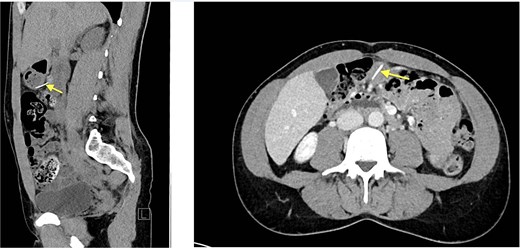

Initial laboratory parameters were unremarkable. Abdominal computed tomography (CT) (03.05.2024) revealed a linear, hyperdense foreign body (Fig. 1)—consistent with a metallic wire—penetrating the anterior gastric wall and abutting the dorsal rectus sheath left paramedian [10]. Minimal free fluid was noted, but no pneumoperitoneum. Two small hepatic lesions were incidentally noted, suggestive of hemangiomas.

Abdominal CT (03.05.2024), hyperdense foreign body (metallic wire).